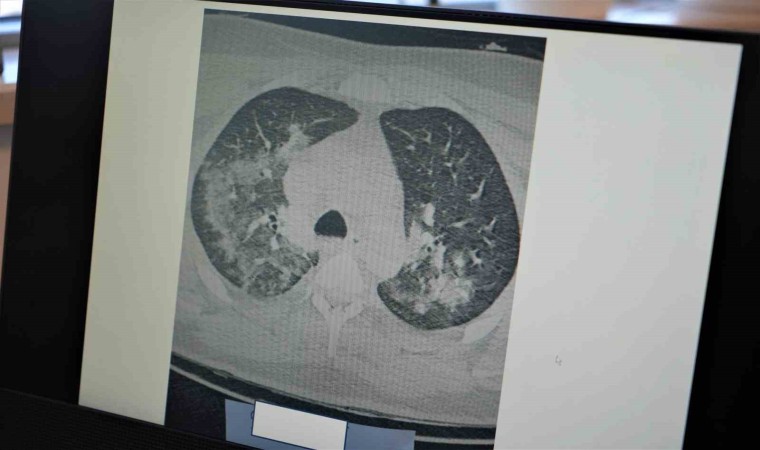

Kovid-19’un damarlarda bıraktığı hasarın önemine dikkat çeken Prof. Dr. Özkaya, "Kovid-19’u yaşadıktan sonra koronanın vücudumuza ne yaptığını öğrendik. Özellikle Kovid-19’dan sonra gerçekten kalp, akciğer ve bütün vücudumuzdaki kılcal damalarımızda hasar oluştu. Bu Kovid-19’un yüküne bağlı olarak sitokin fırtınası dediğimiz bir tablo olan kanın içindeki kan hücreleri taşıyan plazmamızı, kan öz sıvısı öyle tahrip edici hale getirdi ki, damar duvarındaki yapıyı değiştirdi ve bozulmalara neden oldu. Bu durumda pandemi öncesi döneme göre artık damarlarınız da kalıcı hasarlar olabilir. Yaptığınız ağır sporları; halı saha maçı, ağır bisiklet sporları, ağır yüzmeleri pandemi öncesine göre vücudunuz bunları kaldıramayabilir. Hayatı tehdit edici sonuçlar doğurabilir. Ağır sporlar sonrası kalbinizin ve akciğerlerinizin kanını vücudunuz damar hasarı nedeniyle yeterince sağlayamazsa kalp krizleri ve kalp yetmezlikleri ile karşılaşabilirsiniz. Kovid-19 sonrası virüs yükünüze bağlı olarak ortaya çıkan damar duvarındaki değişiklikler kan akımını etkilediği için ağır sporlar sonrası kalp krizleri ve kalp yetmezliği ortaya çıkıyor" diye konuştu.

"Damar embolisi dediğimiz bir tablo var. Bu durumda çok sık görülmeye başladı. Vücuttaki pıhtılaşma probleminin 3 ana sebebi vardır. Birincisi damar duvarı hasarı, ikincisi hareketsiz yaşam, üçüncüsü de genetik yatkınlıktır. Kovid gerçekten pıhtılaşmaya yatkınlık yapan damar duvarı hasarını yaptı. İkinci olan hareketsizlik ise uzun seyahatler, hastalık nedeniyle evde yatmalar sonucu pıhtılaşma oluyor ve buda akciğerlerde damar tıkanıklığına neden oluyor. Bu durum ise ölüme kadar götürüyor. Özellikle sıcak hava ve nemli havalarda ağır sporlarınızı yaparken dikkatli olmanızı öneriyoruz. Gerçekten korona öncesine göre yaptığınız ağır sporlar da vücudunuz sizin kan akışınızı yeterince sağlamayabilir. Uzun süre hareketsiz kalmamanızı öneriyoruz. Özellikle gençlerimizin bu 2 zıt durum olan hem ağır spor hem de hareketsiz yaşama dikkat etmelerini öneriyoruz."